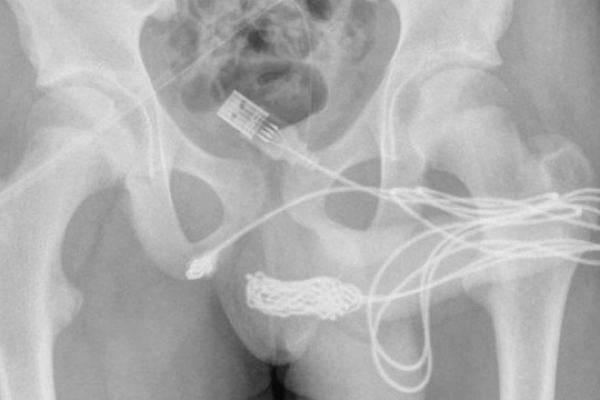

Inusitado

Adolescente é operado após tentar medir o pênis com um cabo USB